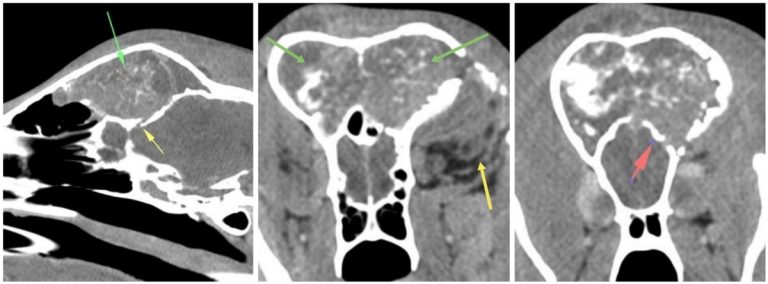

Csontoldódást okozó homloküregi tumor CT felvétele

Távoli áttétek a diagnózis idején rendszerint még nem képződtek, de a betegség előrehaladásával ezek kialakulásának esélye is megnövekszik. A metasztázisok leggyakoribb helye a nyirokcsomók, a tüdő és az agy, ritkábban a környező csontok, szív, máj, vesék, mellékvesék érintettek.